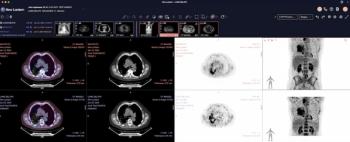

PSMA PET/CT Facilitates Better Long-Term Survival Rates After Salvage Radiotherapy for Recurrent PCa

Patient with biochemical recurrence of prostate cancer who had PSMA PET/CT prior to salvage radiotherapy had better survival rates at one, two and five years, according to newly published research.